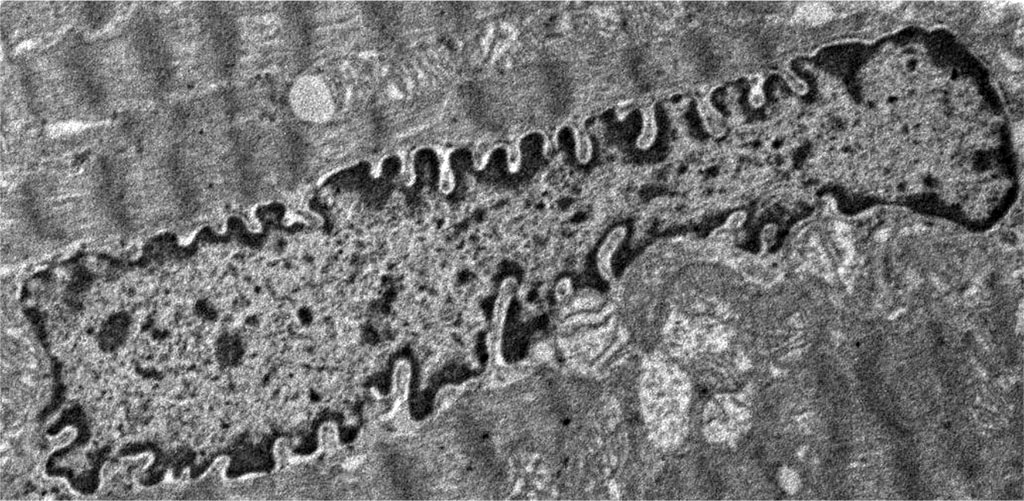

A change in the structure of the nucleus, characterized by an uneven contour of the nuclear membrane, in manifest primary hypothyroidism is a very characteristic phenomenon and was found in electron diffraction patterns of all animals of the experimental group. The contours of the nuclear membrane became tortuous due to the appearance of invaginations, and the shape of the nucleus itself became more wrinkled. Karyolemma invaginations ranged from shallow to very pronounced (Figure 2), while in the control group, the contours of the nucleus were smooth or had a relatively small number of shallow karyolemma invaginations. In a small number of cardiomyocytes, the invaginations of the nuclear membrane were so deep that it gave the impression of a gradual physical separation of the nucleus into separate fragments. Very characteristic changes in hypothyroidism were changes in the structure of the nucleus, expressed in the redistribution of chromatin and its condensation. In the nucleus of cardiomyocytes of intact animals, darker areas (heterochromatin), localized on the periphery in the form of the thinnest rim, and a lighter area (euchromatin), occupying a central position, are noticeable. In the euchromatin area, occasional finely punctate zones of heterochromatin were found. Whereas in the nuclei of cardiomyocytes of animals in the state of hypothyroidism, the heterochromatin rim was more pronounced and in the center of euchromatin an increase in the number and size of heterochromatin areas was noted. Around some nuclei of contractile cardiomyocytes a slight perinuclear edema was found, which is not typical for the nuclei of contractile cardiomyocytes of the intact group of rabbits. According to recent studies, a change in the contours of the nucleus, wrinkling of the nucleus and condensation of chromatin is one of the early signs of cell apoptosis. Thus, our data on structural changes in the nuclei of contractile cardiomyocytes in hypothyroidism are consistent with other researchers, who, using molecular genetic research methods, found activation of proapoptotic and suppression of antiapoptotic signaling pathways and enzymes in a number of cells (cardiomyocytes, neurocytes, macrophages, smooth myocytes, hepatocytes, etc.) in case of hypothyroidism [21-26].

Figure 2. Histopathological changes in the nucleus of contractile cardiomyocytes: overt primary hypothyroidism on the 29th day from the start of the experiment. Magnification 2400. TEM.

Very noticeable ultrastructural changes were found in the contractile apparatus of contractile cardiomyocytes. In animals of the experimental group, thinning of myofibrils was noted, compared with animals in the control group. The characteristic feature was the presence of areas of overcontraction of myofibrils, characterized by a decrease in the size of sarcomeres (a decrease in the distance between telophragms), a decrease in the size of light discs and the H-zone around the mesophragm (Figure 2 and Figure 3).